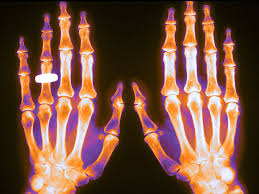

Eficacia de un programa poblacional de rastreo de osteoporosis en mujeres de 70 a 85 años

Se calculó el puntaje FRAX y se realizó densitometría a aquellas con riesgo de fractura elevado, dejando el tratamiento a criterio del médico de cabecera. Se logró una reducción del 28% (IC 11-41%) de las fracturas de cadera. The Lancet, 15 de diciembre de 2017